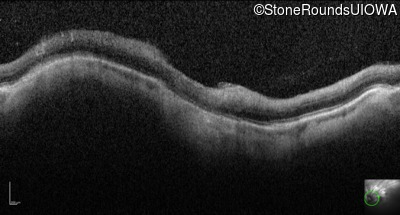

Optical Coherence Tomography - Right - 20/100

Exemplar